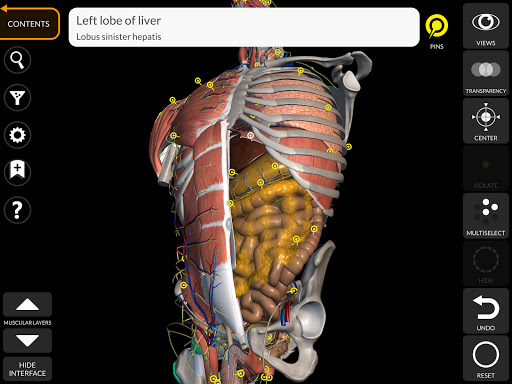

"Anatomy 3D Atlas" дозволяє легко та інтерактивно вивчати анатомію людини.

Завдяки простому та інтуїтивно зрозумілому інтерфейсу можна спостерігати кожну анатомічну структуру під будь-яким кутом.

Анатомічні 3D-моделі особливо деталізовані та мають текстури з роздільною здатністю до 4k.

Поділ за регіонами та попередньо визначені види полегшують спостереження та вивчення окремих частин або груп систем і зв’язків між різними органами.

• Можливість приховування або ізоляції однієї чи кількох вибраних моделей

• Фільтр, щоб приховати або відобразити кожну систему

• Візуалізація м’язів через рівні шарів від поверхневих донизу до найглибших

• Вибравши модель або шпильку, з’явиться відповідний анатомічний термін